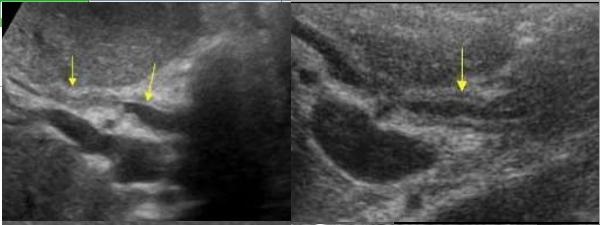

Aspect echographique

d'une cholangite infectueuse aigue de voie

biliaire intrahepatique . Image de

dilatation du canal avec epaissisement a

hypoechogene tres marquee de sa paroi (

fleche jaune ) . Image du calcul du canal

biliaire est en vue a moin nette ( fleche

rouge ) sur ce coupe |

A precoce image

echographique d'une cholangite sclerosant

primitive est image de epaissisement de la

paroi de voie biliaire , en vue de image en

queue de comet . Coupe echographique a

hypochondre droit a travers foie droit . |

Au stade

avance , on peut envoyait image

de epaissisement de paroi des voie biliaire avec de couche

oedemateuse hypoechogene . ( fleche jaune )

.Voie biliaire en dilatee . Image echographique per cutanee du foie

droit . |